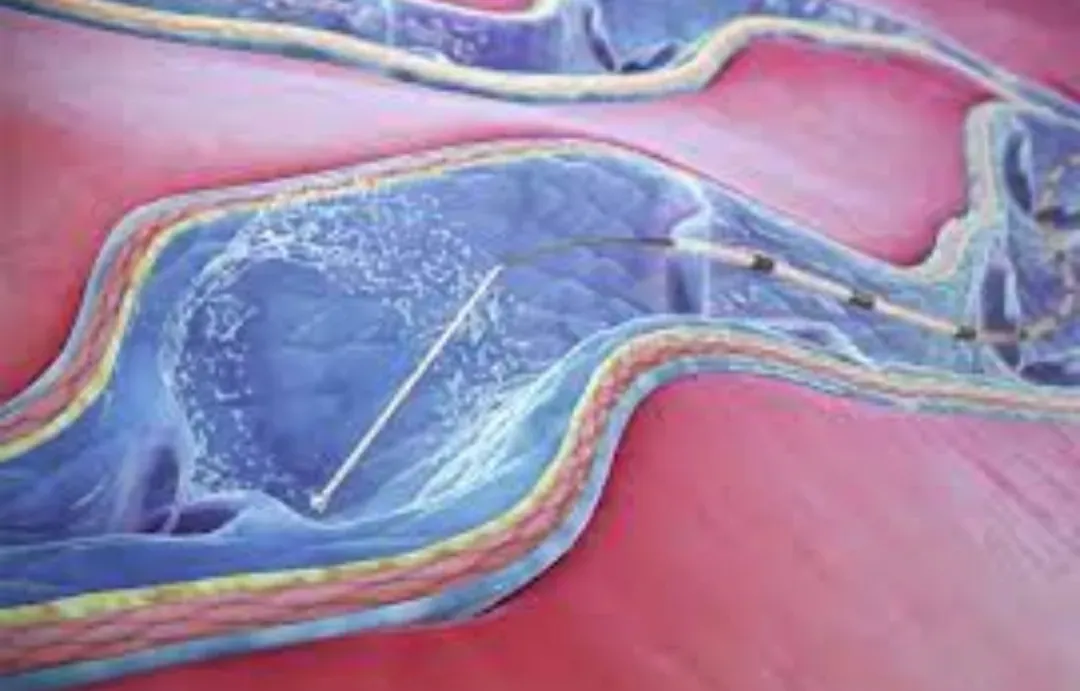

在超声控制下,对IPV进行插管,并在穿支置入消融装置。最初使用射频,后来使用腔内激光。TRLOP在2007年被“重新定义“为“穿支消融术“ (PAPS),尽管两种技术之间没有任何差异。其他工作者通过注射氰基丙烯酸酯胶进一步改进了这一点。TRLOP方法可与这些方法中的任何一种一起用于IPV的局部消融,即使静脉较短。

超声引导下经腔穿支静脉闭塞 (TRansluminal Occlusion of Perforators, TRLOP) 手术。

一些医生主张用UGFS关闭IPV。由于UGFS流经局部静脉,而不会停留在注射部位,因此对IPV进行的UGFS治疗可能导致穿支血管消融不足(泡沫过少),或增加治疗区域局部静脉发生深静脉血栓 (DVT) 的风险(泡沫过多)。因此,尽管已经描述了这一点,但对IPV进行UGFS治疗时,应了解这样做的风险,并且在不可能做TRLOP的情况下进行。